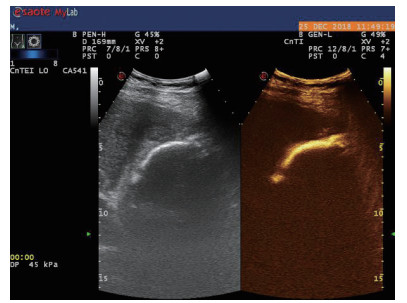

| 图 3 经引流管造影胆囊超声显像,二维图像(左),造影图像(右) |

术后再次经肘静脉超声造影同时经引流管超声造影:PTGBD后,再次经肘静脉快速团注SonoVuel 2 mL,在造影成像模式下进行观察肝脏被膜、胆囊床穿刺路径有无造影剂外渗,腹腔内有无外渗凝聚的造影剂,判断有无活动性出血及出血程度,如判断出血速度快、出血量较大,考虑动脉性出血,及时改为开腹或腔镜手术止血。PTGBD术后经引流管超声造影,置管成功后快速抽出胆囊内残留胆汁,减轻胆囊压力后,在超声造影模式下直接经引流管注入配制待用的稀释声诺维造影剂20 mL,实时动态的观察造影剂在胆囊腔内的充盈范围(图 2、3),评估引流管的通畅程度及引流范围、观察其在胆囊腔内的位置走形及卷曲情况、观察胆囊周边及腹腔内有无造影剂外渗。如患者腹痛症状加剧,结合经引流管超声造影判断有胆汁漏出表现,应持续监测观察患者生命体征及保守治疗效果,必要时及时改行开腹或腔镜手术治疗。

超声造影是利用超声造影剂微泡(本组应用的是声诺维超声造影剂微泡)在低机械指数声波照射下发生共振,产生线性及非线性谐波回声信号,形成造影增强图像的技术,是近年来新兴的超声技术,具有实时、可连续观察、无辐射、可重复性好、毒不良反应少等优势,为临床提供了全新的诊疗手段[14]。经肘静脉注入的标准配置超声造影剂是一种血池造影剂,可以反映组织的血流灌注情况同时亦被广泛应用于肝、脾、肾等实质性脏器破裂的诊断,其诊断的敏感性及特异性均明显优于二维超声,且与增强CT有较好的一致性[15-16]。本组病例术前经肘静脉注入标准配置造影剂后,胆囊壁均显影增强,胆囊穿孔及周边积液处表现为造影无充盈区,穿刺置管后再次静脉路超声造影,迅速发现术后出血部位且可敏感评估是否为活动性出血(经手术证实)。除1例因活动性出血中转腹腔镜手术外,其余32例置管成功后经引流管口注入稀释造影剂20 mL(1:200稀释),评价引流管位置、引流范围及是否出现胆汁外漏取得良好效果,所有引流导管均能够清晰显示引流导管置入路径、引流管形态及引流范围,引流管置入恰当者,头端位于胆囊内,全管显影清晰,造影剂弥散区域与胆囊大小吻合; 置管后胆汁漏出者,可见造影剂沿引流管周边渗出[17-18],本组中3例出现造影剂外渗,其中两例渗出范围局限于胆囊床附近,未渗出至游离腹腔,患者腹痛症状稍有加剧,经胆囊减压及对症处理后好转,其中1例见造影剂渗出至肝肾间隙,患者腹痛症状加剧明显,考虑置管位置不当,余行急诊腹腔镜手术治疗,术中证实为系膜胆囊,且可见引流管侧孔部分外露。笔者的经验是,术前选择静脉路超声造影有助于对胆囊情况的评估及穿刺点的选择,术中正确选择穿刺针的入路有利于提高穿刺引流的成功率。首先是胆囊穿刺部位的选择应选择在靠近胆囊颈侧,此处胆囊位置比较固定,受体位影响较小,且胆囊床结缔组织较为固定,有助于将漏出胆汁包裹局限,其次是进针方向与胆囊床尽可能保持垂直,减少进针位置的偏移,同时置管成功后应即刻尽量抽尽胆囊内的感染性胆汁,生理盐水冲洗后行经引流管稀释超声造影有助于判断置管位置、引流范围及是否出现胆汁漏出,减少不必要的并发症发生率。穿刺引流后可以根据患者的营养状况待窦道形成稳定后择期拔除引流导管。对全身情况改善适合手术治疗且有手术意愿者可以考虑择期胆囊切除术。